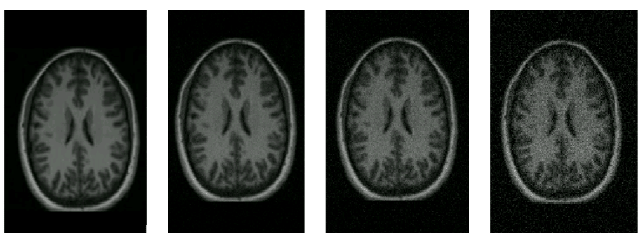

For each misregistered image set, Specificity and Generalisation were calculated, as described in Section 6.2, using $m$ = 15 modes of variation for the model and $\mathcal{M}$ = 1000 synthetic images drawn from a Gaussian model distribution. This was repeated for values of shuffle radius, $r$, of 1 (Euclidean distance), 1.5, 2.1 and 3.7, as defined in Section [*], corresponding to circular neighbourhoods contained within 1x1, 3x3, 5x5 and 7x7 pixel patches respectively. These experiments were repeated with 2.5%, 5.0% and 10% Gaussian intensity noise added to the misregistered images, in order to investigate the sensitivity of the model-based measures to image noise. This makes it possible to argue in defence of the robustness of these measures to noise. Figure [*] shows an example brain image with varying degrees of noise added.

Figure: effect of varying the level of noise applied to the original image (left). Noise levels of 0%, 2.5%, 5%, and 10% (right) are shown.